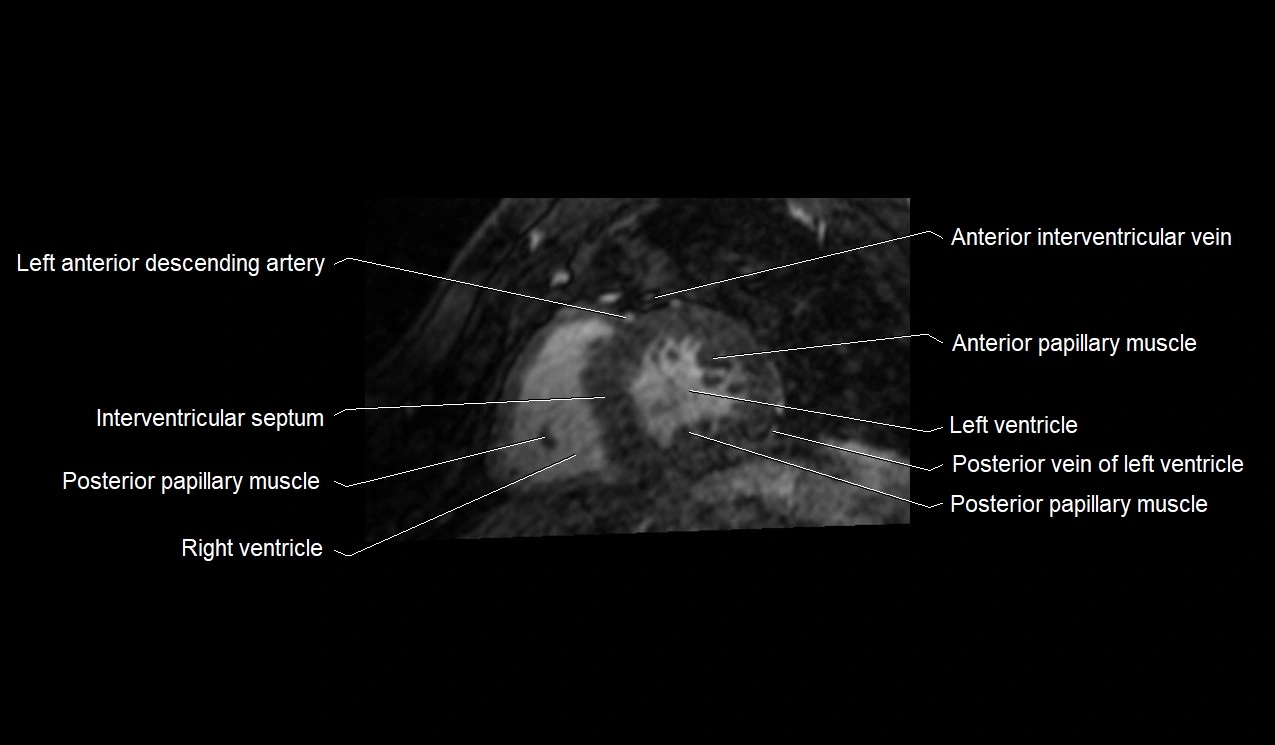

MRI image